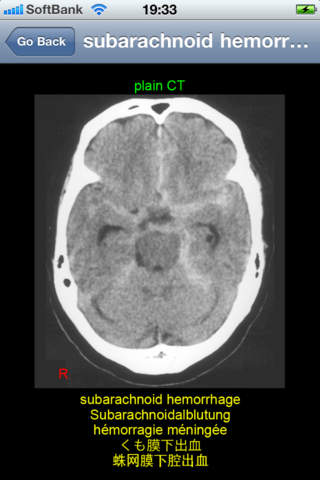

This application is developed to study neuroradiology in English, German, French, Japanese, and Chinese for medical students and professionals such as physicians and nurses. It consists of 26 diagnosis: acoustic neurinoma, acute epidural hematoma, ADEM, aneurysm, arachnoid cyst, arteriovenous malformation, astrocytoma, cerebellar atrophy, cerebral embolism, cerebral hemorrhage, cerebral infarction new and old, cervical disc herniation, chronic subdural hematoma, colon carcinoma metastasis, depressed skull fracture, glioblastoma multiforme, hemorrhagic infarction, meningioma, multiple sclerosis, OPLL, osteoma, pineal cyst, pontine hemorrhage, putaminal hemorrhage, subarachnoid hemorrhage, and syringomyelia.